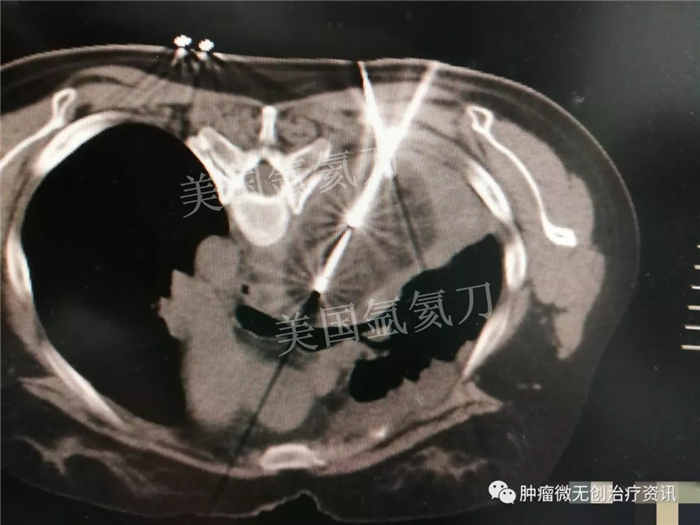

中日友好医院氩氦刀冷冻消融治疗胸膜间皮瘤

30岁女性患者,因胸膜间皮瘤,就诊于中日友好医院中西医结合肿瘤内科。结合患者情况,行氩氦刀冷冻消融治疗。此次手术的主要目标为减瘤。